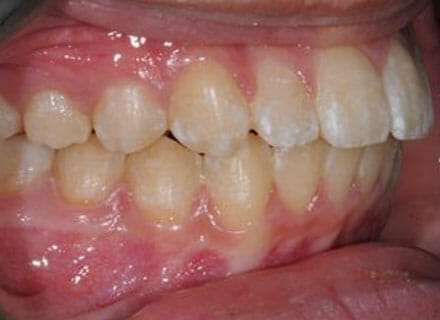

Fixing protruding teeth upper and lower and crowding – no extractions

this patient didn’t like the teeth because they pushed forwards and were sticking out and pushing out her lips. She thought that she looked like she had too many teeth and not enough space. In 12 months we pulled all the teeth back, pulled them together, and lined them all up. No teeth were extracted because we made room by expanding the jaws.